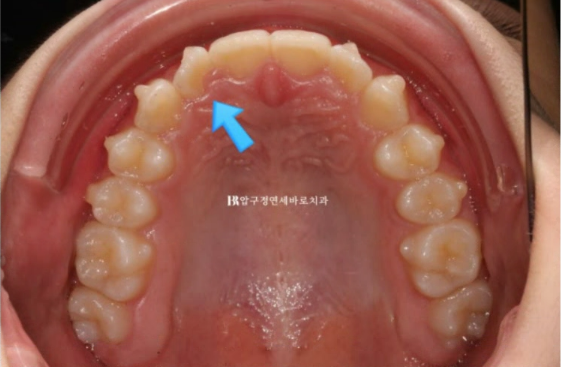

23.11

14단계를 모두 끼고 난 후 사진을 보면 파란 화살표 부분 덧니가 아직 100% 원래 자리로 돌아가지 못 했습니다.

이 부분은 처음부터 의도한 부분입니다.

클린체크를 보면 애초에 치료계획상에서 덧니를 80%만 돌린 것을 알 수 있습니다.

인비절라인 라이트는 14단계 안에 허용되는 범위 안에서만 부정교합 개선이 가능하기 때문입니다.

나머지 20%의 회전은 전략적으로 추가장치에서 잡으면 됩니다.

이렇게 하면 굳이 처음에 비용이 비싼 인비절라인컴프리헨시브로 하지 않아도 100% 개선이 가능합니다.

앞니 회전과 디테일한 부분을 추가로 개선하기 위해서 구강스캔을 하고 추가장치 제작에 들어갑니다.